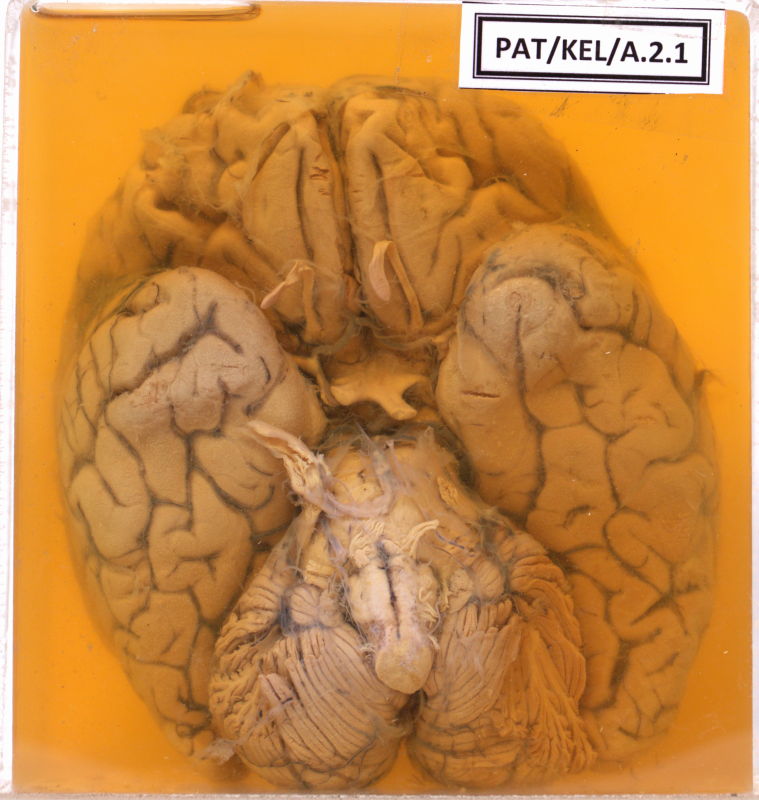

A.2.1 Meningitis

Thick exudates covering the brain surface.

The gyri are flattened & sulci are narrow.

Prominent vasculature over the surface of the brain are seen.